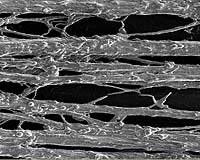

A close-up of stretch grown axons

To create the interface, the team used a newly developed process of stretch growth of nerve fibers called axons, previously pioneered in Smith's lab. Two adjacent plates of neurons are grown in a bioreactor. Axons sprout out to connect the neuron populations on each plate. The plates are then slowly pulled apart over a series of days, aided by a precise computer-controlled motor system, until they reached a desired length.

For the interface, one of the plates is an electrical microchip. Because Smith and his team have shown that stretch-grown axons can transmit active electrical signals, they propose that the nervous-tissue interface - through the microchip - could detect and record real-time signals conducted down the nerve and stimulate the sensory signals back through the axons.